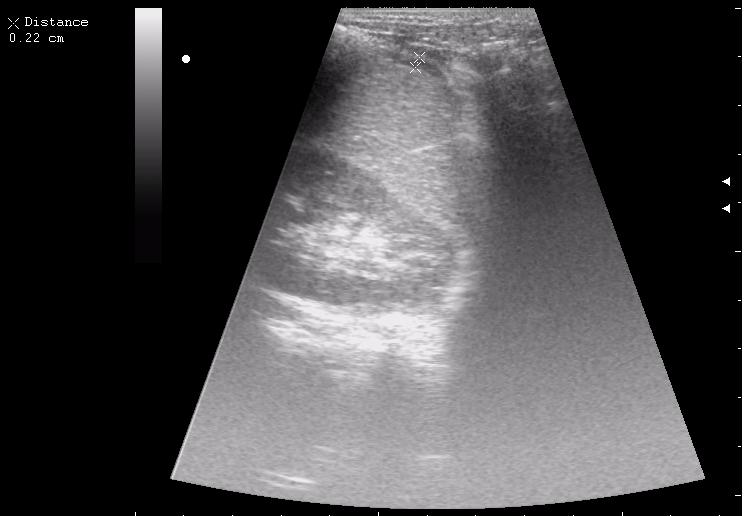

наезд большой черной Прады на маленькую (13кг) 5-летнюю девочку.

получает Медаксон, рабочая версия - изменение желчного пузыря вследствии травмы (шепотом - рекомендация хирургу сменить антибиотик)